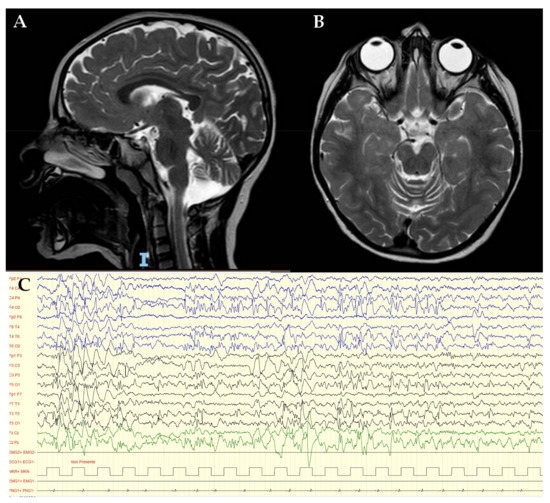

3.1. Clinical Report